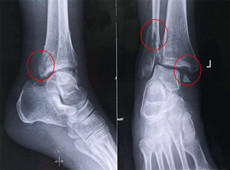

【醫(yī)療科普】踝關(guān)節(jié)骨折的主要類型及其影像學(xué)表現(xiàn)

大家好,我是南京醫(yī)科大學(xué)第二附屬醫(yī)院骨科副主任醫(yī)師王伯堯,從事骨科臨床工作十余年,擁有豐富的骨科臨床經(jīng)驗(yàn),主要研究方向?yàn)楣强剖中g(shù)機(jī)器人的開(kāi)發(fā)與臨床應(yīng)用,今天跟大家介紹踝關(guān)節(jié)骨折的幾種常見(jiàn)類型及其在X影像上的表現(xiàn)。接下來(lái)跟...